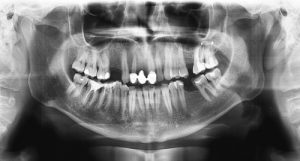

Een röntgenfoto wordt gemaakt met behulp van elektromagnetische straling, die vrij gemakkelijk door de zachte weefsels en minder makkelijk door de harde weefsels dringt. Het verschil van doorlaatbaarheid van de weefsels ten aanzien van de straling, vertaalt zich in een twee dimensionaal zwart-wit beeld op de foto.

Met behulp van röntgenfoto’s zijn wij in staat om duidelijke en goede diagnoses te kunnen stellen. In sommige gevallen kunnen we niet altijd de conditie van het gebit bepalen met het blote oog. Daarom maken we als aanvulling van de halfjaarlijkse controle om de zoveel tijd controlefoto’s. Dit zijn vaak twee foto’s, van de linker en de rechterkant van uw kaak, om zo goed al uw (kleine) kiezen te kunnen beoordelen.

In de meeste gevallen is dit een preventieve maatregel, zodat wij beginnende problemen al snel kunnen oplossen of zelfs kunnen voorkomen.

Bij wortelkanaalbehandelingen, implantologie of bij chirurgische behandelingen, worden er over het algemeen altijd röntgenfoto’s gemaakt.

Bij deze behandelingen is het noodzakelijk om röntgenfoto’s te maken, om zo de behandeling zo voorspelbaar mogelijk te kunnen uitvoeren.

Ook is het soms nodig om bij een pijnklacht een röntgenfoto te maken van de desbetreffende tand of kies die last geeft. Met behulp van een foto kunnen wij goed lokaliseren waar het probleem vandaan komt.

De straling die vrij komt van deze röntgenfoto’s is zo laag, dat de kans op nadelige gevolgen erg klein is. In principe kunnen er zelfs röntgenfoto’s gemaakt worden tijdens de zwangerschap. Toch geven wij er de voorkeur aan om geen onnodige risico’s te nemen en zullen wij de röntgenfoto’s die niet noodzakelijk zijn, uitstellen tot na de bevalling.